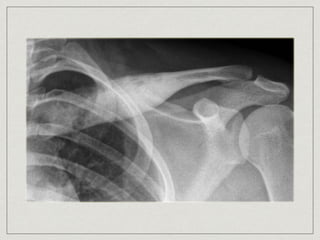

Osteochondroma

most common benign bone neoplasm

(50% all benign rib tumors)

painless mass

arise from metaphyseal region of rib and

develops as stalked mass with

cartilaginous cap

male x3 > female

complete surgical resection of treatment of

choice

Osteochondroma most common benignbone neoplasm (50% all benign rib tumors) painless mass arise from metaphyseal region of rib and develops as stalked mass with cartilaginous cap male x3 > female complete surgical resection of treatment of choice